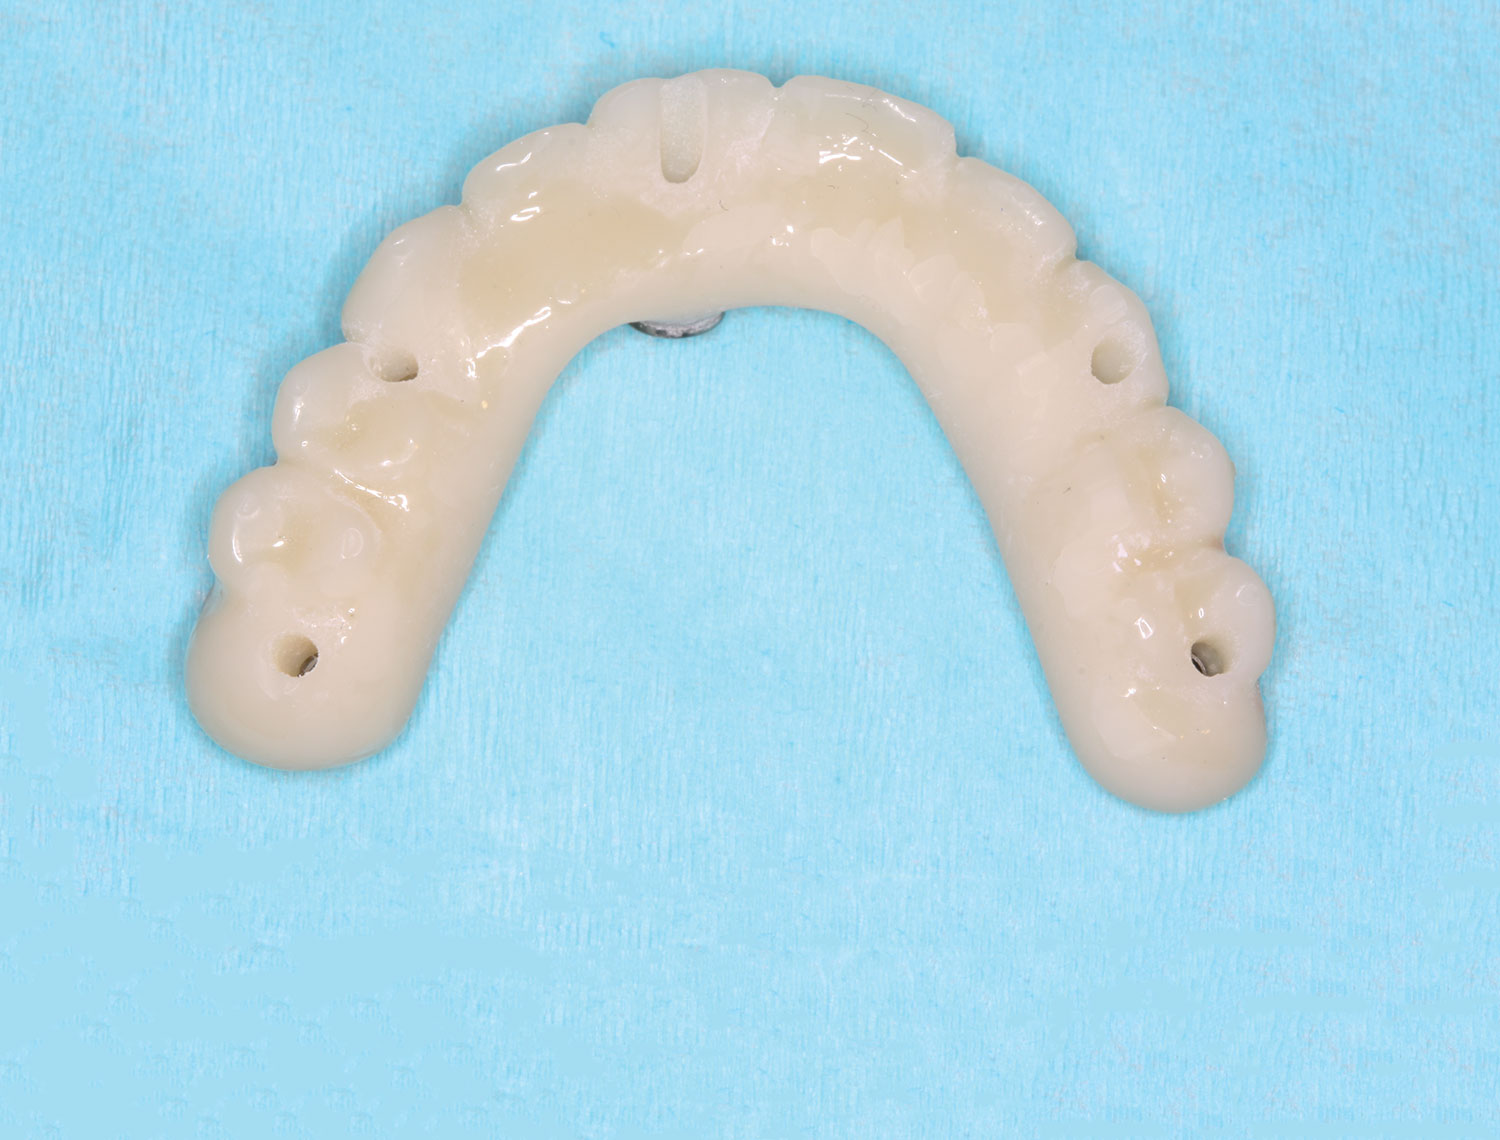

Fig 16. Maxillary provisional prosthesis printed and ti-bases inserted.

Figure 16

Fig 17. Maxillary provisional prosthesis with screw-access holes in prosthetically correct locations.

Figure 17

Several hours later the dental team received the STL file, from which they would print the maxillary prosthesis on a 3D printer using appropriately colored nanoceramic resin. The prosthesis was stained and glazed, and metal cylinders were inserted into the undersurfaces

of the screw-access holes, each of which was specifically located to fit on the multi-unit abutments (Figure 16 and Figure 17).